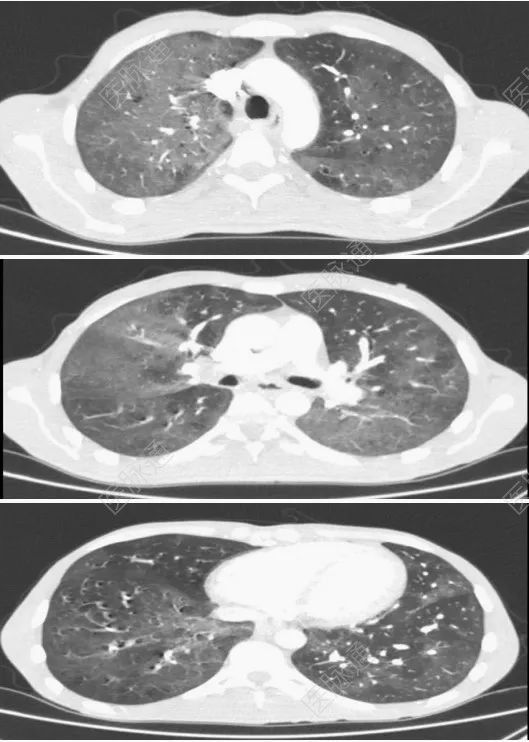

CT显示双肺弥漫性磨玻璃影,右上叶更为明显;左下区双肺局灶性实质密度差异明显;空气囊腔和隔旁

患者CT结果